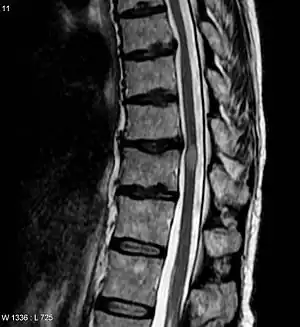

| MRI acute myelitis | |

Myelitis is inflammation of the spinal cord which can disrupt the normal responses from the brain to the rest of the body, and from the rest of the body to the brain. Inflammation in the spinal cord, can cause the myelin and axon to be damaged resulting in symptoms such as paralysis and sensory loss. Myelitis is classified to several categories depending on the area or the cause of the lesion; however, any inflammatory attack on the spinal cord is often referred to as transverse myelitis.

Myelitis has an extensive differential diagnosis. The type of onset (acute versus subacute/chronic) along with associated symptoms such as the presence of pain, constitutional symptoms that encompass fever, malaise, weight loss or a cutaneous rash may help identify the cause of myelitis. In order to establish a diagnosis of myelitis, one has to localize the spinal cord level, and exclude cerebral and neuromuscular diseases. Also a detailed medical history, a careful neurologic examination, and imaging studies using magnetic resonance imaging (MRI) are needed. In respect to the cause of the process, further work-up would help identify the cause and guide treatment. Full spine MRI is warranted, especially with acute onset myelitis, to evaluate for structural lesions that may require surgical intervention, or disseminated disease.[11] Adding gadolinium further increases diagnostic sensitivity. A brain MRI may be needed to identify the extent of central nervous system (CNS) involvement. Lumbar puncture is important for the diagnosis of acute myelitis when a tumoral process, inflammatory or infectious cause are suspected, or the MRI is normal or non-specific. Complementary blood tests are also of value in establishing a firm diagnosis. Rarely, a biopsy of a mass lesion may become necessary when the cause is uncertain. However, in 15–30% of people with subacute or chronic myelitis, a clear cause is never uncovered.[9]